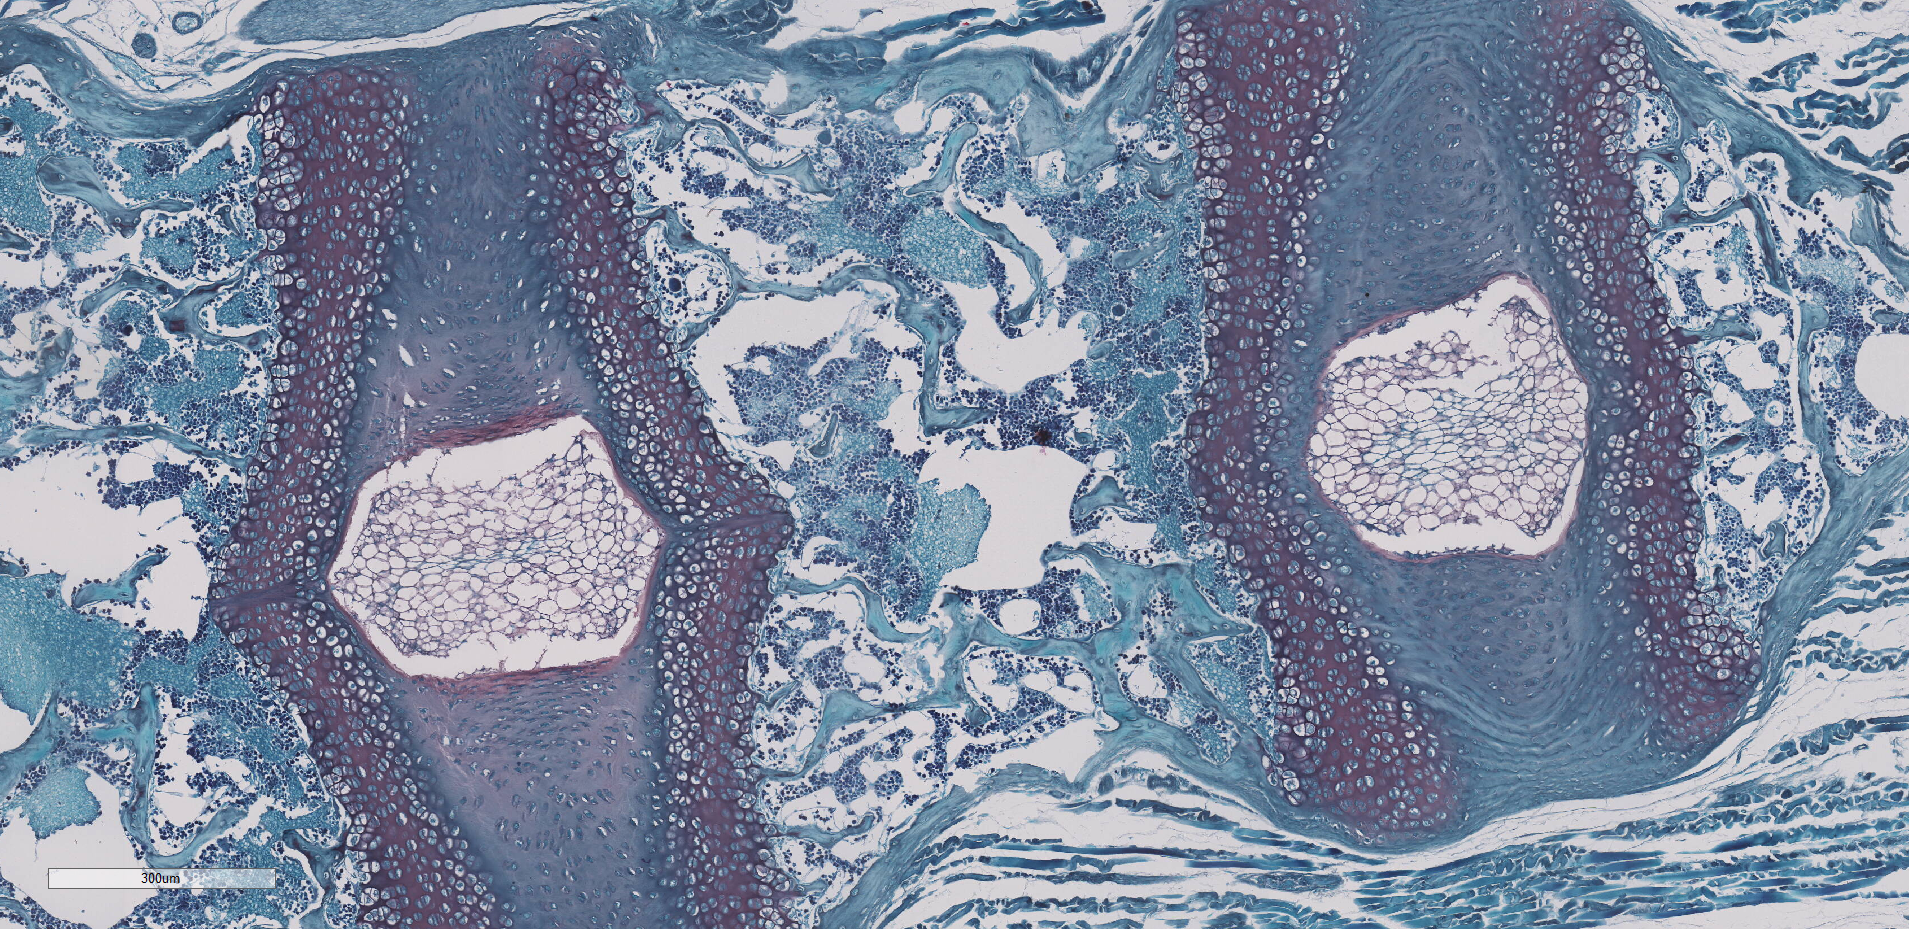

番红固绿染色

改良番红 O-固绿软骨染色法的染色原理在于嗜碱性的软骨与碱性染料番红O结合呈现红色,嗜酸性的骨和酸性染料固绿结合而成绿色或蓝色,与呈现红色的软骨对比鲜明,从而将软骨组织和骨组织区分开。

小鼠 腰椎 番红固绿染色